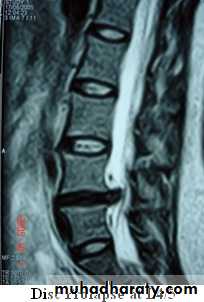

X-rays: show an abnormal narrowed disc space and to exclude bone diseases. After several attacks the disc space may be narrowed and small osteophytes appear.CT and MRI are more reliable than myelography.

CHRONIC INTERVERTEBRAL DISC DEGENERATIONMRI:

Bulging of the annulus fibrosus in both sagittal and axial projections and diminished thickness and reduced signal intensity (dehydration) of the degenerating disc.